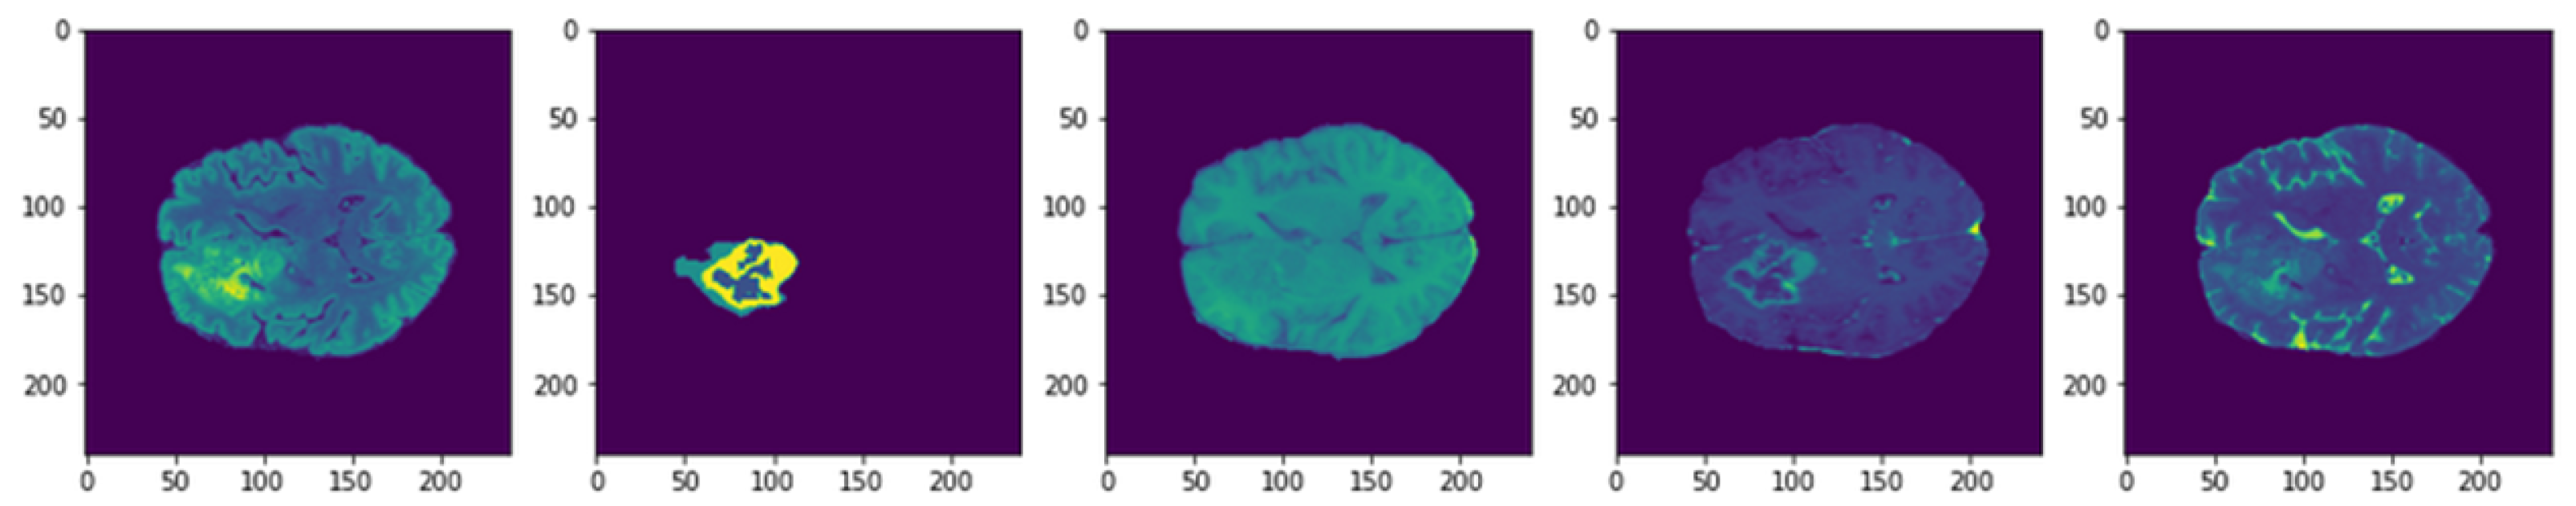

The used dataset is BRaTS 2021 Task 1 Dataset [44]. As training, validation, and testing data for this year’s BraTS challenge, a sizable number of multi-institutional regular clinically acquired multi-parametric MRI (mpMRI) images of glioma with pathologically confirmed diagnosis and accessible MGMT promoter methylation status are used. For Task 1, the datasets utilized in this year’s competition have been updated with many additional routines clinically collected mpMRI scans since BraTS’20. To quantitatively assess the projected tumor segmentations, expert neuroradiologists create and approve ground truth annotations of tumor sub-regions for each patient in the training, validation, and testing datasets. As shown in Figure 3, the dataset is partitioned into a train, validation, and test datasets. Figure 4 illustrates an example of the dataset.

Figure 4.

Example of dataset images.

There are four classes in the segmentation process. Segmentation classes are NOT tumor, non-enhancing tumor (RED color), EDEMA (Green color), and ENHANCING (yellow color). These classes were converted into three classes later. Figure 8 illustrates samples of images and masks with a positive brain tumor. For more precious and fast detection of brain tumor, the 3D U-net segmentation model has been implemented on the BRaTS 2021 dataset. The dataset is divided into 70% training, 20% validation, and 10% testing. Implementation is constructed online on Kaggle. U-net model enhances segmentation validation accuracy up to 99.33%, and validation loss up to 0.01 as shown in Figure 9. We can conclude that our proposed model can detect brain tumor with high accuracy compared to state-of-the-art techniques in terms of classification and segmentation.